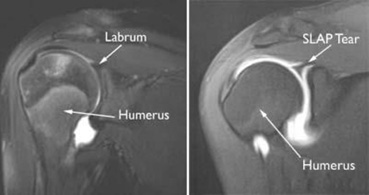

MRI: Not recommended in older patients solely for identifying SLAP lesions. SLAP lesions in older patients are largely asymptomatic and MRI can lead to overdiagnosis. MRI is useful in younger patients (<35 years old) and can be made even more sensitive with the use of contrast (MR arthrogram).

Image 9 [12]. The labrum is seen as a dark triangle in a normal shoulder. SLAP tears are evidenced by bright signaling where there would otherwise be a lack of signal.

Image 10 [12]. SLAP tear indicated by white signal in what would normally be a pure black triangle of the labrum.